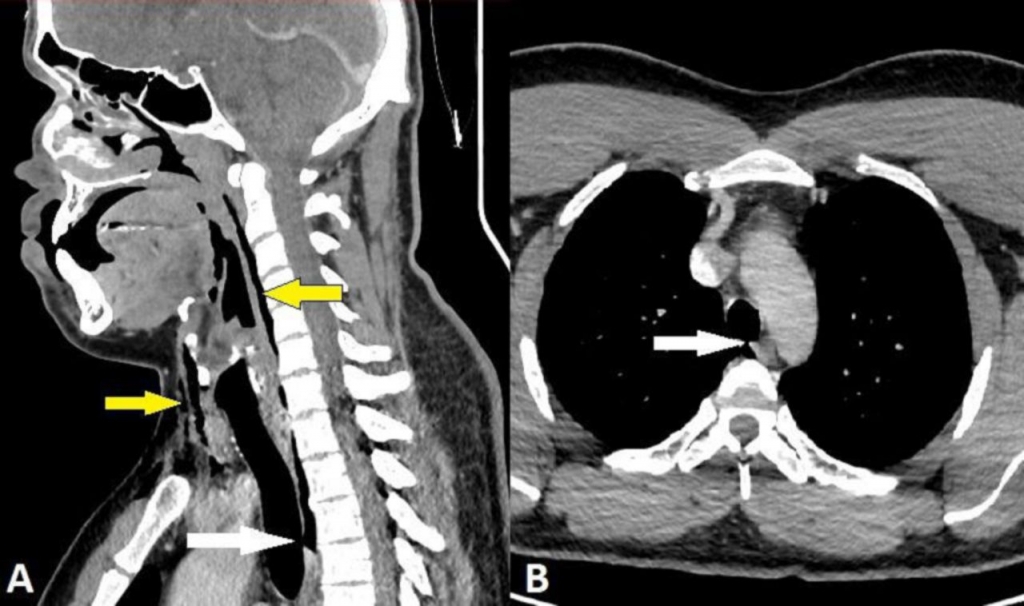

알레르기성 비염을 앓던 30대 스코틀랜드 남성은 자동차를 운전하던 중 재채기가 나왔다. 하지만 재채기가 나오는 시점에 코를 막고 입을 다물었다가 심한 목 통증을 겪었다고 한다. 결국 남성은 응급실로 향했고 정밀 진단을 실시했다.

그 결과 기관지가 찢어져 가로·세로 각 2㎜ 크기 구멍이 생겼다. 일부 폐기종 증상도 나타났다. 폐기종은 기관지나 폐에 염증이 생기고 이로 인해 숨을 쉴 때 폐포가 제 기능을 못하는 질환이다. 만성적 기침이 동반되며 심할 경우 호흡 곤란 증상이 나타난다. 목 통증으로 인해 목의 움직임 범위도 줄어들었다.

연구팀은 "재채기 후 기관지 천공(Perforation·구멍)이 발생한 사례는 이전에 보고된 적이 없다"며 "재채기 중 상부 기도의 압력은 1~2㎪(킬로파스칼) 수준이지만 입과 코를 닫으면 압력이 최대 20배까지 증가할 수 있다"고 밝혔다.

연구팀은 환자가 응급실 내원 당시 수술은 필요없다고 봤지만 징후가 완화하는지 이틀간 병원에서 모니터링했다. 환자는 이후 의사로부터 2주간 격렬한 신체 활동을 하지 말라고 권고받았으며 진통제와 꽃가루 알레르기 비염 약을 처방받고 퇴원했다. 환자는 5주 후 찢어진 부분이 완전히 치유됐다.

연구팀은 이번 사례가 드물지만 위험한 사례라고 밝혔다. 특히 기관 천공은 잠재적으로 생명을 위협하고, 찢어진 부분과 환자의 활력 징후에 따라 수술이 필요할 수 있다는 게 연구팀의 설명이다.